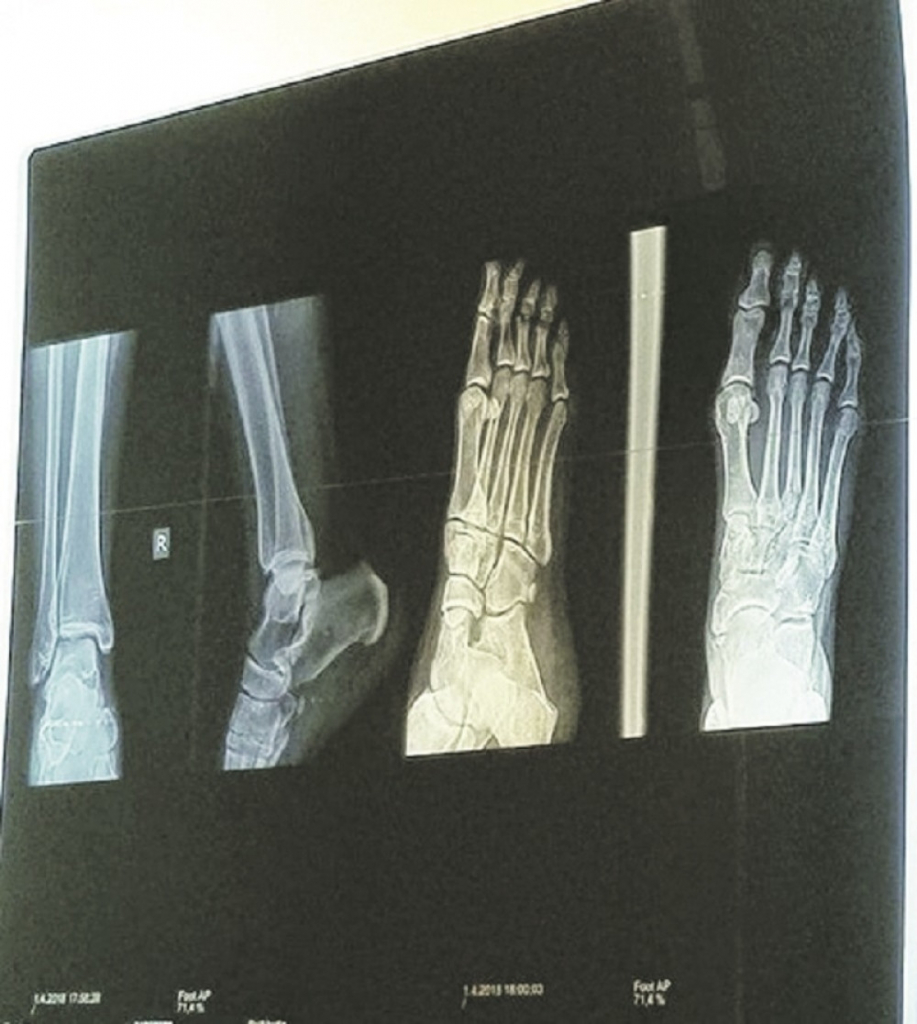

Naime, ona je osetila jake bolove u nozi, da bi se nakon detaljnog pregleda ispostavilo da je reč o povredi skočnog zgloba. Kako VIP saznaje, ona je posle dva dana otišla na rendgensko snimanje, međutim uprkos tome što joj je radiološki tehničar napravio snimak iz više uglova, nisu uspeli da vide u čemu je problem.

- Ona je dobila terapiju koja će trajati oko nedelju dana, a nakon toga, ako se situacija ne smiri, moraće da ide na još jedno snimanje. Dušica se uplašila da može doći do operacije u slučaju da se nešto zakomplikuje. Kako joj je lekar rekao, nakon pucanja ligamenta, razlila se voda u skočnom zglobu i to može da joj napravi ozbiljne komplikacije. Iako joj je lekar otkrio da se takve situacije dešavaju kod ljudi koji imaju slabije mišiće, ipak i njega brine činjenica da rendgenski snimak nije pokazao promene u stopalu i zglobu, te ga čudi da Dušica ima tako jake bolove - otkriva naš izvor.

Voditeljka "Zadruge", nakon terapije koja se sastoji od fizikalnih procedura, počeće sa vežbama koje dodatno utiču na regeneraciju i reparaciju tkiva, a u slučaju da se bolovi nastave, moraće da ide na snimanje magnetnom rezonancom.